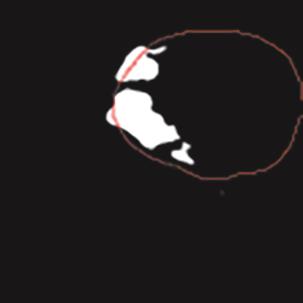

乳腺癌是全球女性最常见的恶性肿瘤之一,准确的病变分割对于乳腺癌的早期诊断与治疗具有重要意义。然而,由于病变形态的多样性以及超声成像机制的复杂性,现有基于深度学习的乳腺超声图像病变分割方法在分割准确性方面仍面临巨大挑战。为进一步提升乳腺超声图像中病变区域的分割精度,该文基于经典U-Net架构,提出了一种新型乳腺超声图像病变分割网络(CWSASKM-BBAM-Net)。首先,在网络中引入逐通道空间自适应选择核卷积模块(CWSASKM),根据不同通道的语义特征为每个空间位置自适应选择感受野大小,以增强多尺度信息的建模能力;然后,引入双向边界感知机制(BBAM),通过融合正向与反向注意力,对目标显著区域及其边界进行协同建模,同时逐步提升对非显著区域与病变区域的区分能力,以进一步强化边界信息的表达;最后,在3组公开乳腺超声图像数据集(BUSI、UDIAT和STU)上开展分割实验。结果表明:该方法在数据集BUSI上的杰卡德指数、精确率、召回率和Dice相似系数分别为71.97%、82.85%、81.40%和80.44%,较次优方法分别提升1.69、1.05、1.28和1.84个百分点;在数据集UDIAT上,这4项指标分别达到78.14%、88.31%、86.73%和86.10%,较次优方法分别提升了2.75、2.04、0.56和2.01个百分点;在外部数据集STU上,该方法也取得了优于其他方法的整体表现。实验结果表明,CWSASKM-BBAM-Net在乳腺超声图像分割任务中展现出更优的整体性能。